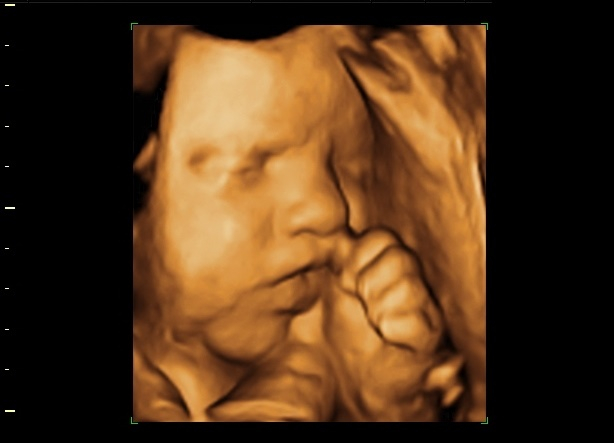

4D ultrazvuk predstavlja najsavremeniji način pregleda trudnica, gde se ultrazvučni talasi softverskim putem pretvaraju u sliku fetusa, koja je izuzetno jasna i fascinantna roditeljima koji sve vreme mogu da posmatraju svoju još nerođenu bebu. Na ovaj način veza između roditelja i bebe postaje još jača.

4D ultrazvuk ima i četvrtu dimenziju-vreme i na taj način se dobija prikaz pokreta fetusa u realnom vremenu. Kada je u pitanju kasnija faza trudnoće, mogu se, pored pokreta i celokupne anatomije u sklopu video snimka uočiti i istezanje, češkanje, sisanje prstića, mrštenje, osmeh fetusa.